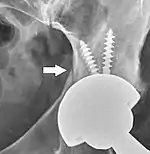

Hemiarthroplasty

Hemiarthroplasty is a surgical procedure that replaces one half of the joint with an artificial surface and leaves the other part unchanged. This class of procedure is most commonly performed on the hip after an intracapsular fracture of the femur neck (hip fracture). The procedure is performed by removing the head of the femur and replacing it with a metal or composite prosthesis. The most commonly used prosthesis designs are the Austin Moore and Thompson prostheses. A composite of metal and HDPE that forms two interphases (bipolar prosthesis) can be used. The monopolar prosthesis has not been shown to offer any advantage over bipolar designs. The procedure is recommended only for elderly/frail patients, due to their lower life expectancy and activity level. This is because over time the prosthesis tends to loosen or to erode the acetabulum.[86] Independently mobile older adults with hip fractures may benefit from a total hip replacement instead of hemiarthroplasty.[87]

Hip prosthesis for hemiarthroplasty. This example is bipolar, meaning that the head has two separate articulations.

X-ray of the hips, with a right-sided hemiarthroplasty